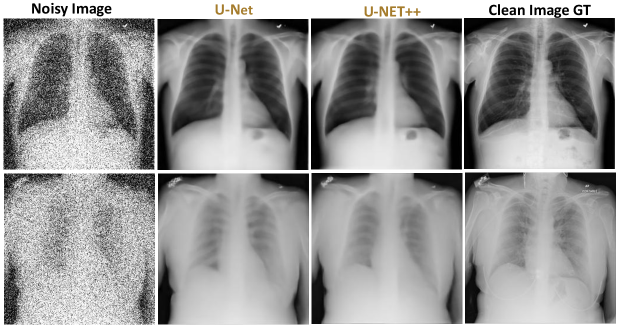

To qualitatively assess image reconstruction fidelity, we compare denoising outputs at 10%, 20%, and 30% Gaussian noise levels using representative test samples. Each comparison (Done under 1-GPU configurations) includes the noisy input, U-Net output, U-Net++ output, and the clean ground truth.

Figures 56, and 7 illustrate results at 10%, 20%, and 30% noise levels, respectively.

As shown in Figure 5, U-Net produces relatively clean reconstructions, though some residual speckle noise remains. U-Net++, by contrast, yields sharper edge definitions and restores anatomical continuity more faithfully. Structures such as ribs, clavicles, and lung boundaries exhibit enhanced contrast. In particular, the apical regions show smoother transitions and more precise rib contours. The visual SSIM appears higher for U-Net++, with better preservation of brightness consistency and edge contrast.

Figure 5: Visual comparison of noisy input, U-Net and U-Net++ denoised outputs, and ground truth (10% noise levels).